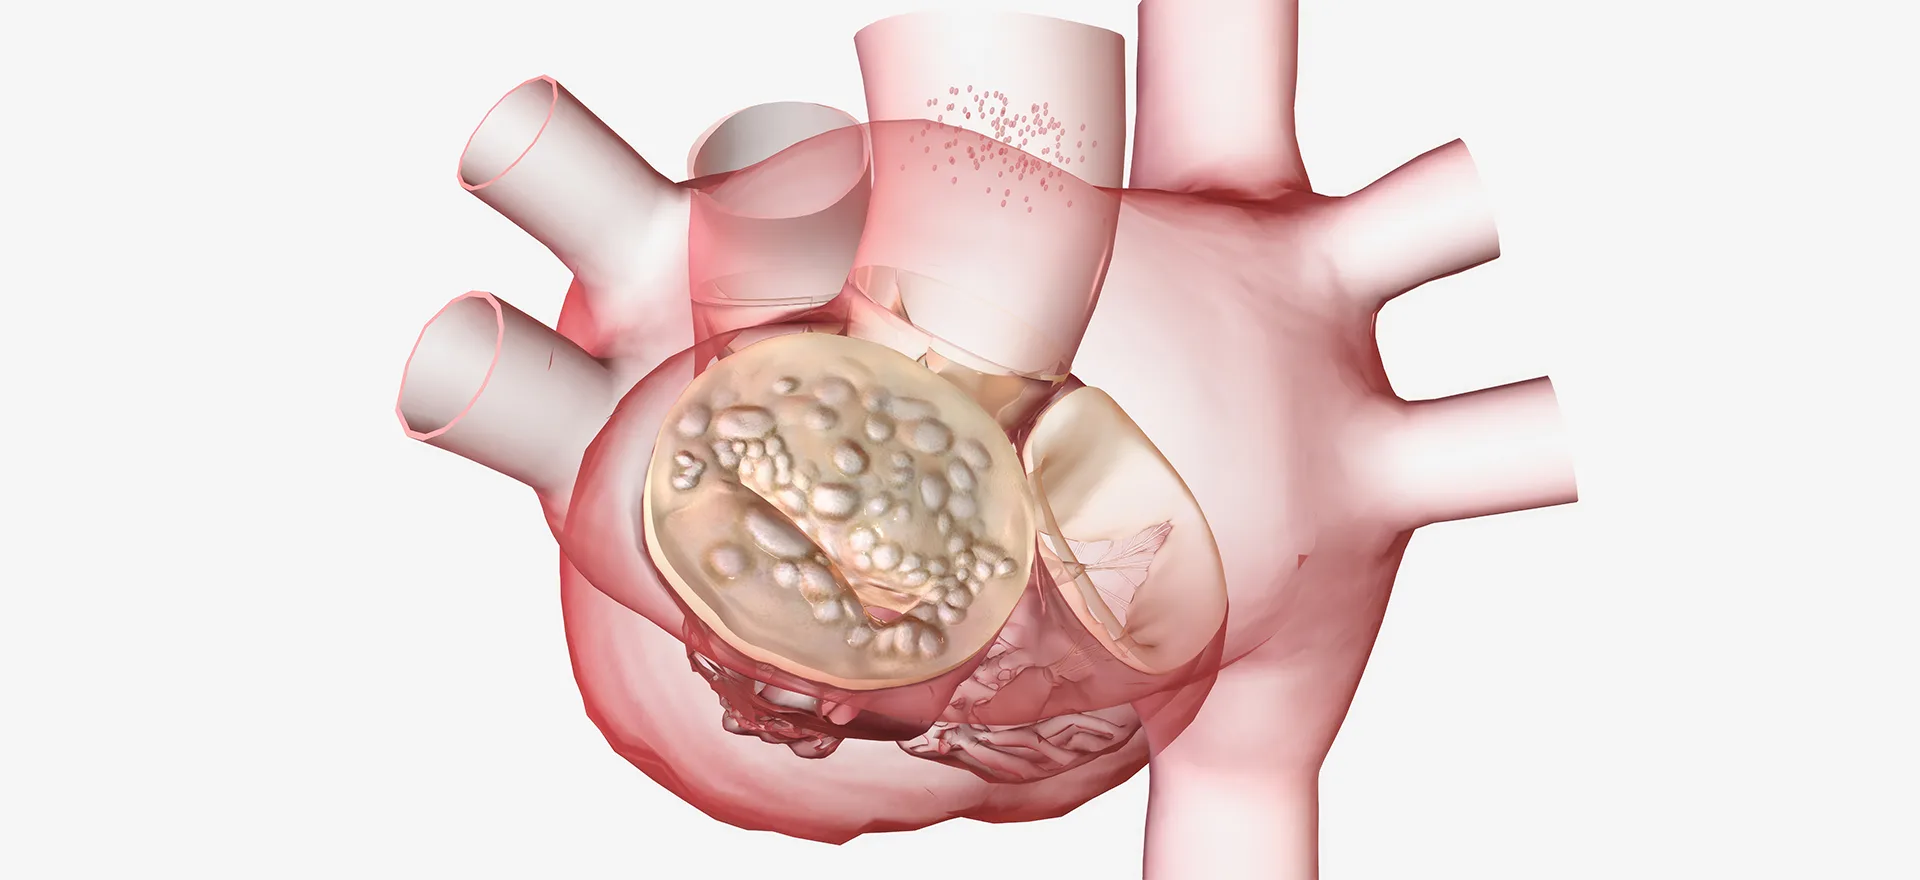

The valve between the left atrium and left ventricle of the heart is called the mitral valve. Mitral stenosis can be defined as the mitral valve opening, which controls blood flow in the heart, being narrower than normal. Mitral stenosis restricts the flow of blood from the left atrium to the left ventricle, which pumps blood to the body. Blood that is prevented from passing into the left ventricle accumulates in the left atrium much more than normal. Thus, the left atrium begins to enlarge and arrhythmias occur. If the enlargement of the left atrium continues to increase, arrhythmias called atrial flutter and then atrial fibrillation develop. Atrial fibrillation is important because this arrhythmia disrupts the contraction function of the left atrium, slows blood flow in the left atrium, and ultimately causes blood clots to form within the left atrium. If this clot moves and enters the systemic circulation, embolisms and strokes may occur.

What Are the Causes of Mitral Stenosis?

The mitral valve, which prevents blood from leaking backward through the valve and ensures blood flow, narrows in certain conditions. There are many factors that can cause mitral stenosis. These factors can be listed as follows:

Rheumatic Fever: Rheumatic fever, which can develop after throat infections, can damage the heart valves.

Congenital Factors: Some patients may have congenital mitral valve stenosis and abnormalities.

Endocarditis: Endocarditis, an infection that infects the inner surface of the heart, can lead to mitral stenosis.

Degenerative mitral valve disease

Mitral annular calcification

Malignant carcinoid syndrome

The mitral valve, which ensures the heart functions regularly and oxygenated blood flows to the body, may not perform its function in various conditions. Mitral stenosis is one of the conditions that affect heart function. Stenosis prevents adequate blood flow to the systemic circulation and causes an increase in pulmonary pressure as a result of blood pooling in the lungs.